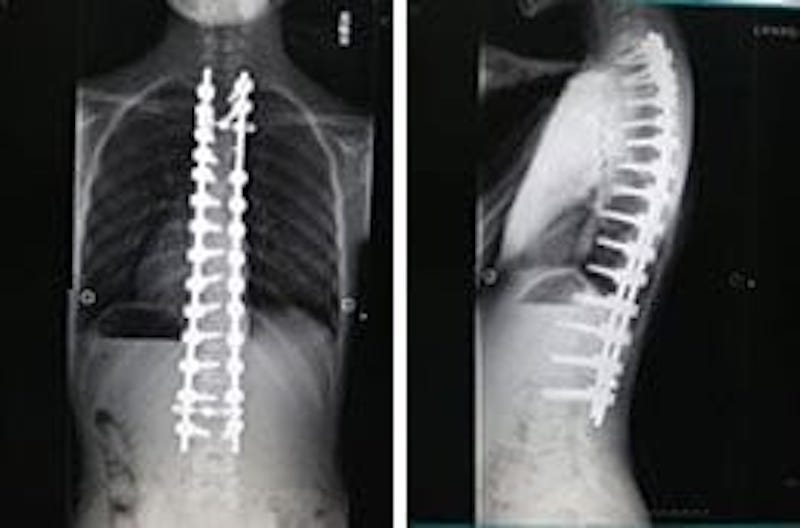

小児脊柱変形治療に関する最新の知見を提供する専門書。- タイトル: 小児脊柱変形治療の最前線- 著者: 川上恵明, 学野晴行- 出版社: 南江堂- 言語: 日本語- 学会: 日本脊椎矯正学会購入しましたが、必要なくなり、読んではおらず開いていない状態です。購入当初からだったと思いますが、カバーに多少のスレと引っかき傷があります。(3枚目写真)